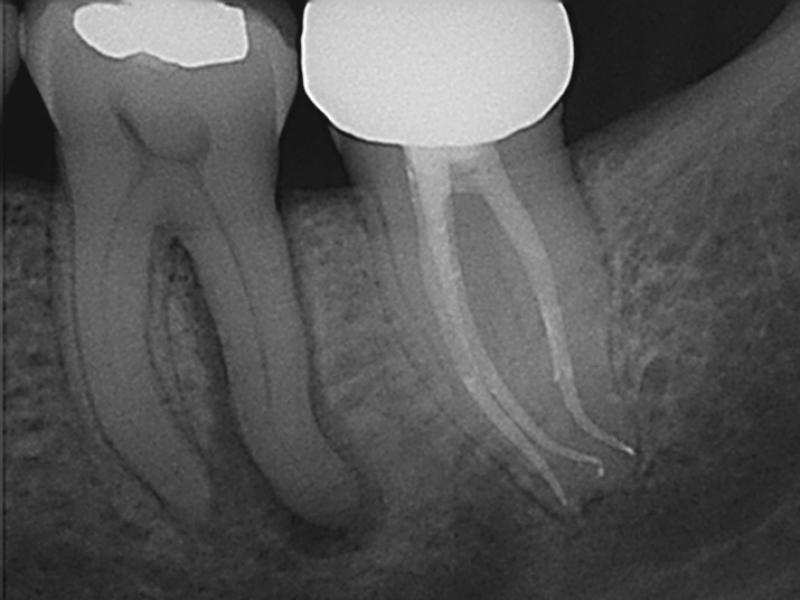

Recall

Guarded Pre-Op with 3 Months Healing Evidence